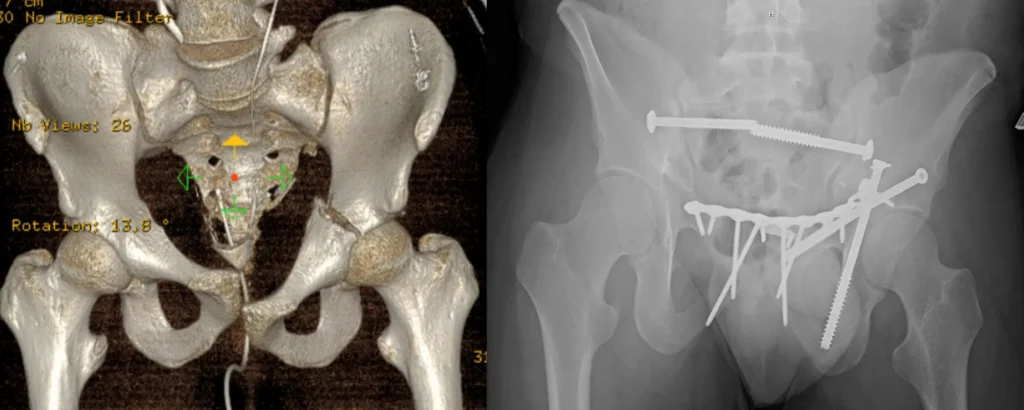

Combined surgical fixation acetabulum and total hip for geriatric acetabulum fracture

Combined surgical fixation acetabulum and total hip for geriatric acetabulum fracture